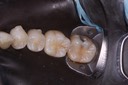

Photos of Clinical Operations

Drs. Peter Kearney, Terry McKay, John St. Germain, and Laurie Vanzella - Mentors